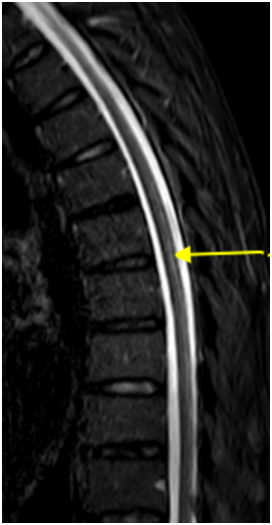

半年前,王先生開始感覺走路不穩(wěn),像踩在棉花上,還伴有肢體麻木無力。這些癥狀逐漸加重,最終他來到鄭州大學(xué)第五附屬醫(yī)院神經(jīng)內(nèi)科二病區(qū)就診。檢查發(fā)現(xiàn),他患有巨幼紅細胞性貧血,維生素B12水平明顯偏低。脊髓磁共振結(jié)果顯示:胸段脊髓后索出現(xiàn)異常高信號(如圖黃色箭頭所示),軸位圖上更是呈現(xiàn)出典型的倒“V”征(綠色箭頭)。